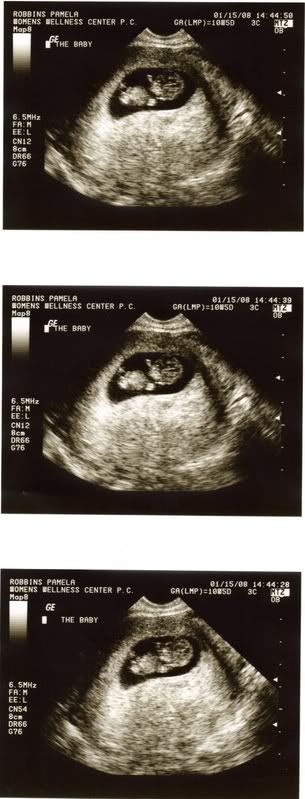

U/S photos

My3LilMonkeys wrote: Here's my little peanut at 9 weeks 6 days.

CantWait replied: Look at that little peanut, s/he looks so well developed already.

Calimama replied: Aw, he/she looks like SUCH a little baby already!!